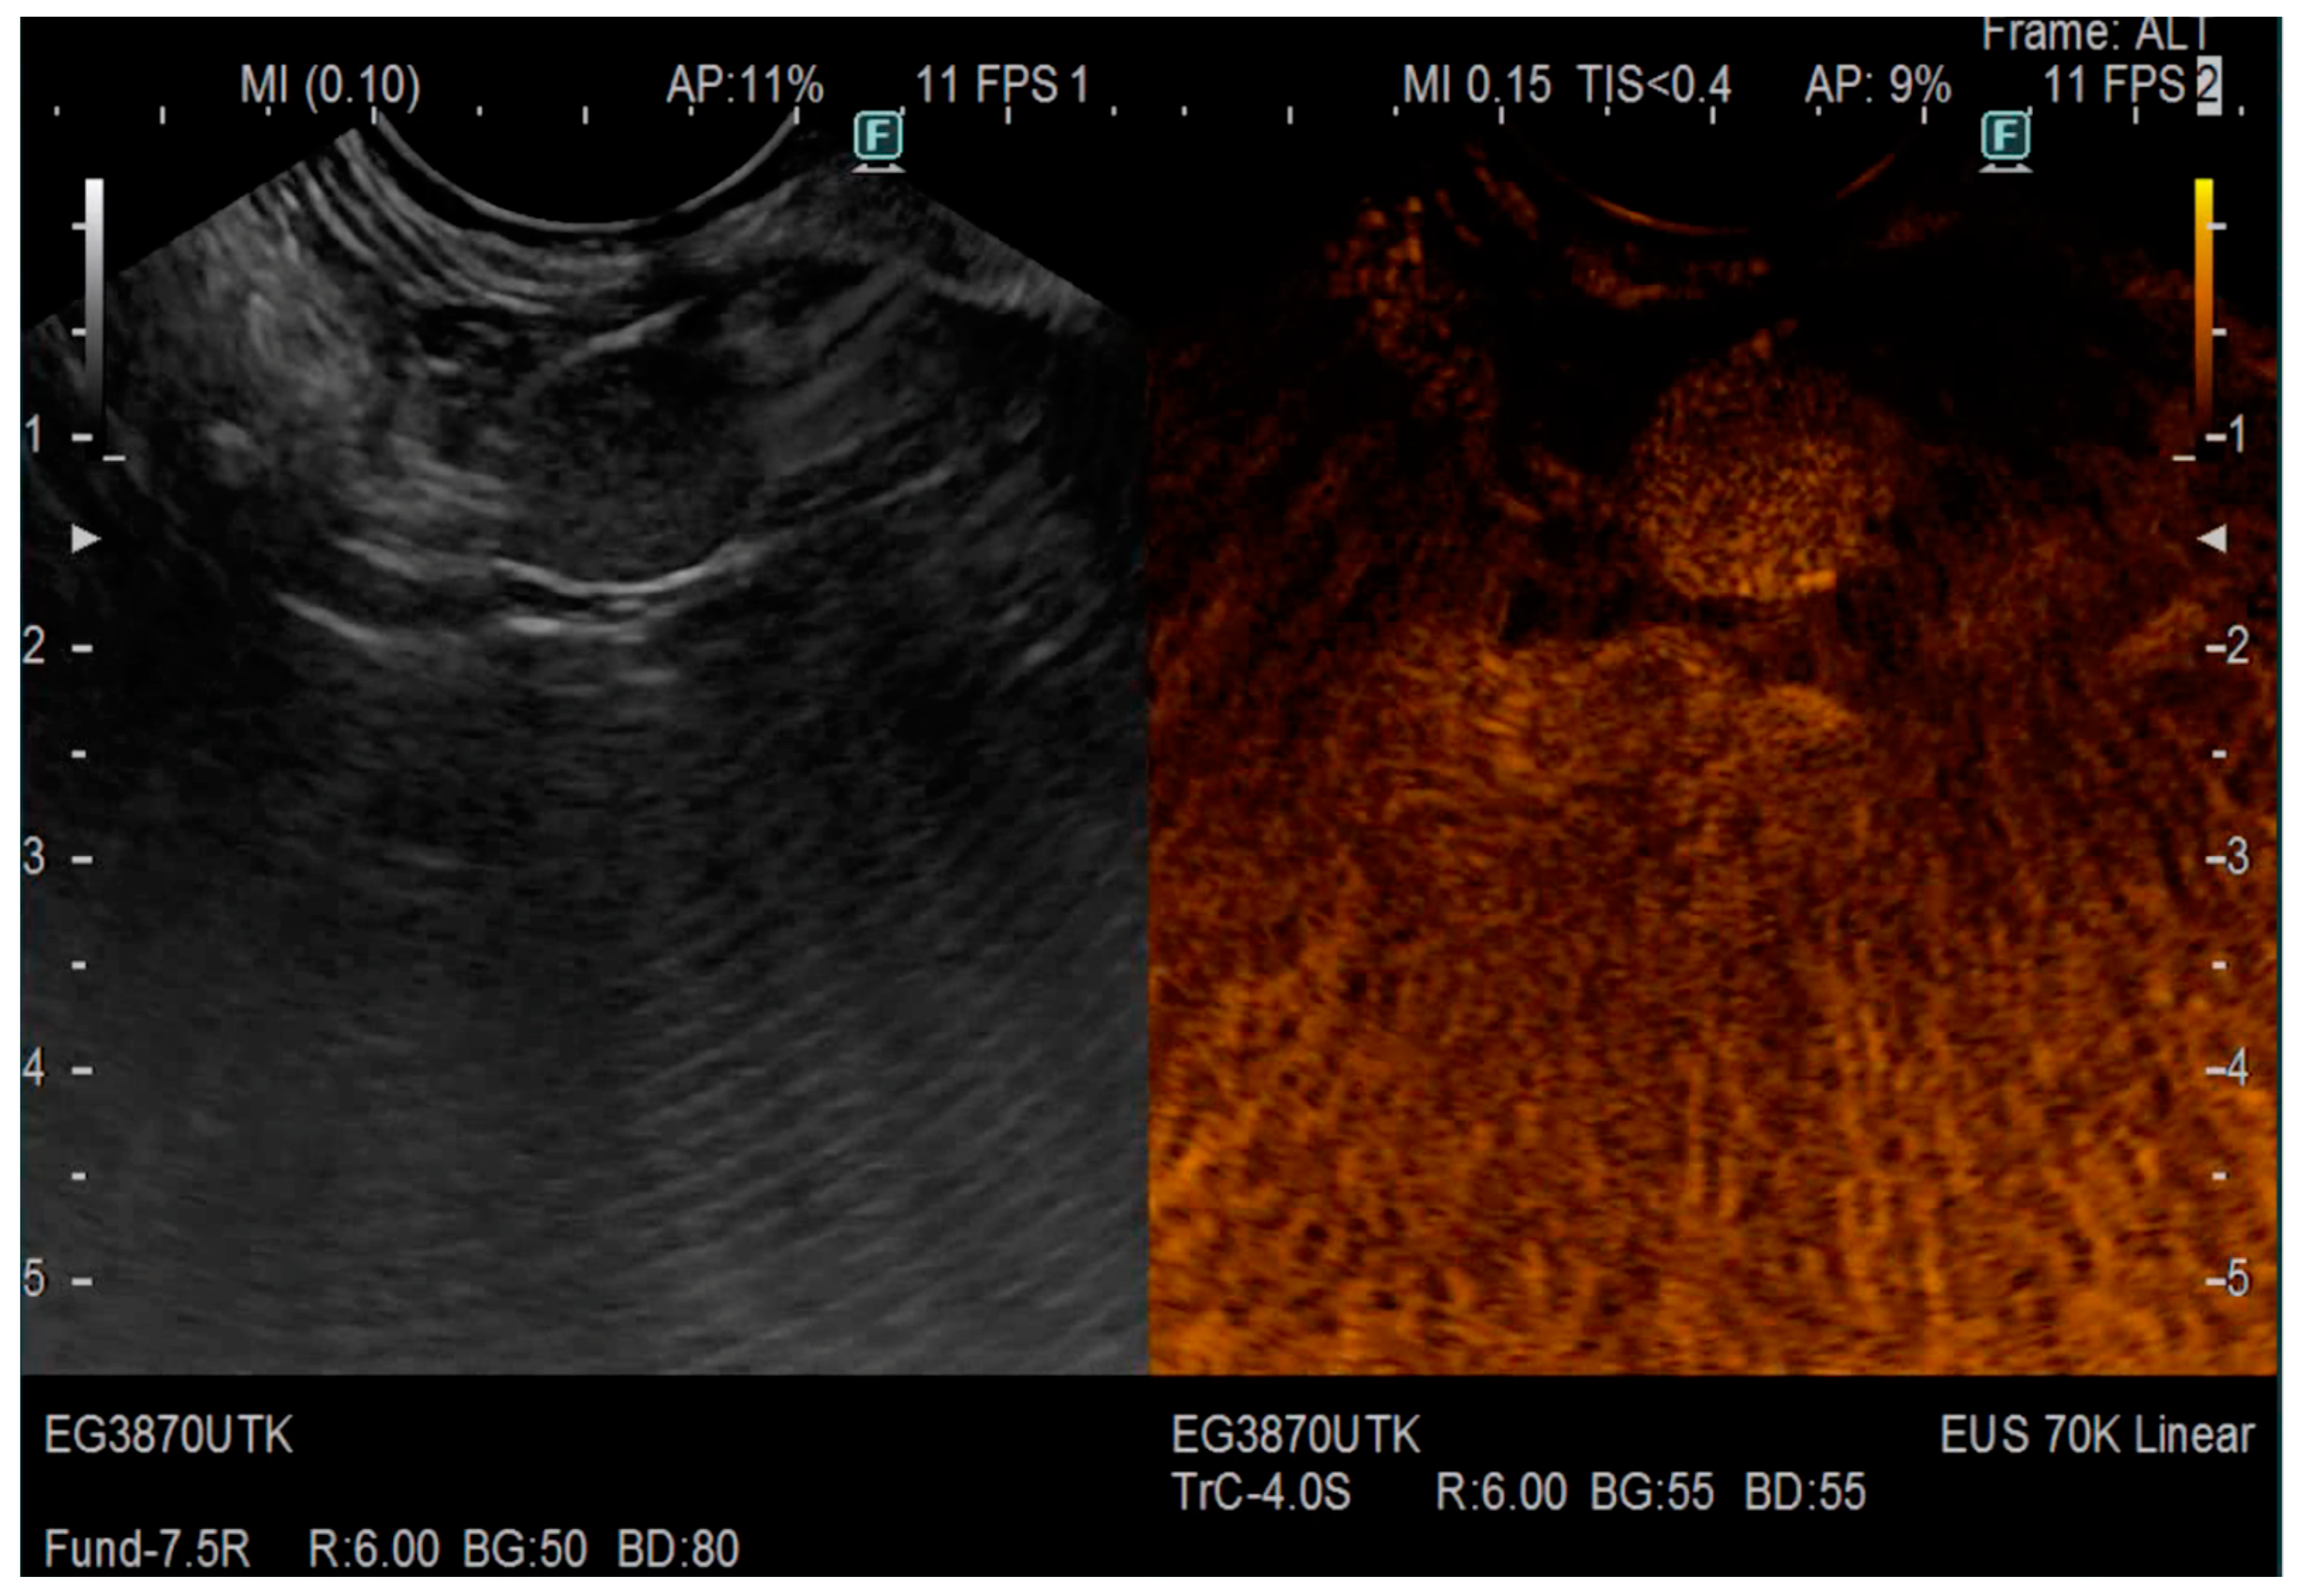

| Pathology | Examination | Features |

|---|---|---|

| Pancreatic cancer | EUS | Hypoechoic mass with irregular borders, dilatation of the proximal PD |

| EUS elastography | The mean SH value (the overall hardness of a lesion) is lower than 80 | |

| CE-EUS | Iso-enhancement or hypo-enhancement, arterial irregularity and absent venous vasculature within a mass | |

| Chronic pancreatitis | EUS-elastography | Hyperechoic foci with shadowing and MPD calculi and lobularity with honeycombing |

| CE-EUS | Hyper-enhanced lesions with preserved architecture | |

| PNETs | CE-EUS | Hypervascularization, a low microvessel architecture |

| Autoimmune pancreatitis | EUS | Diffuse hypoechoic areas, diffuse enlargement, bile duct wall thickening and peripancreatic hypoechoic margins |

| CE-EUS | Hypervascularization, focal or diffuse iso-enhancement | |

| EUS-elastography | Homogeneous stiffness of the whole organ |